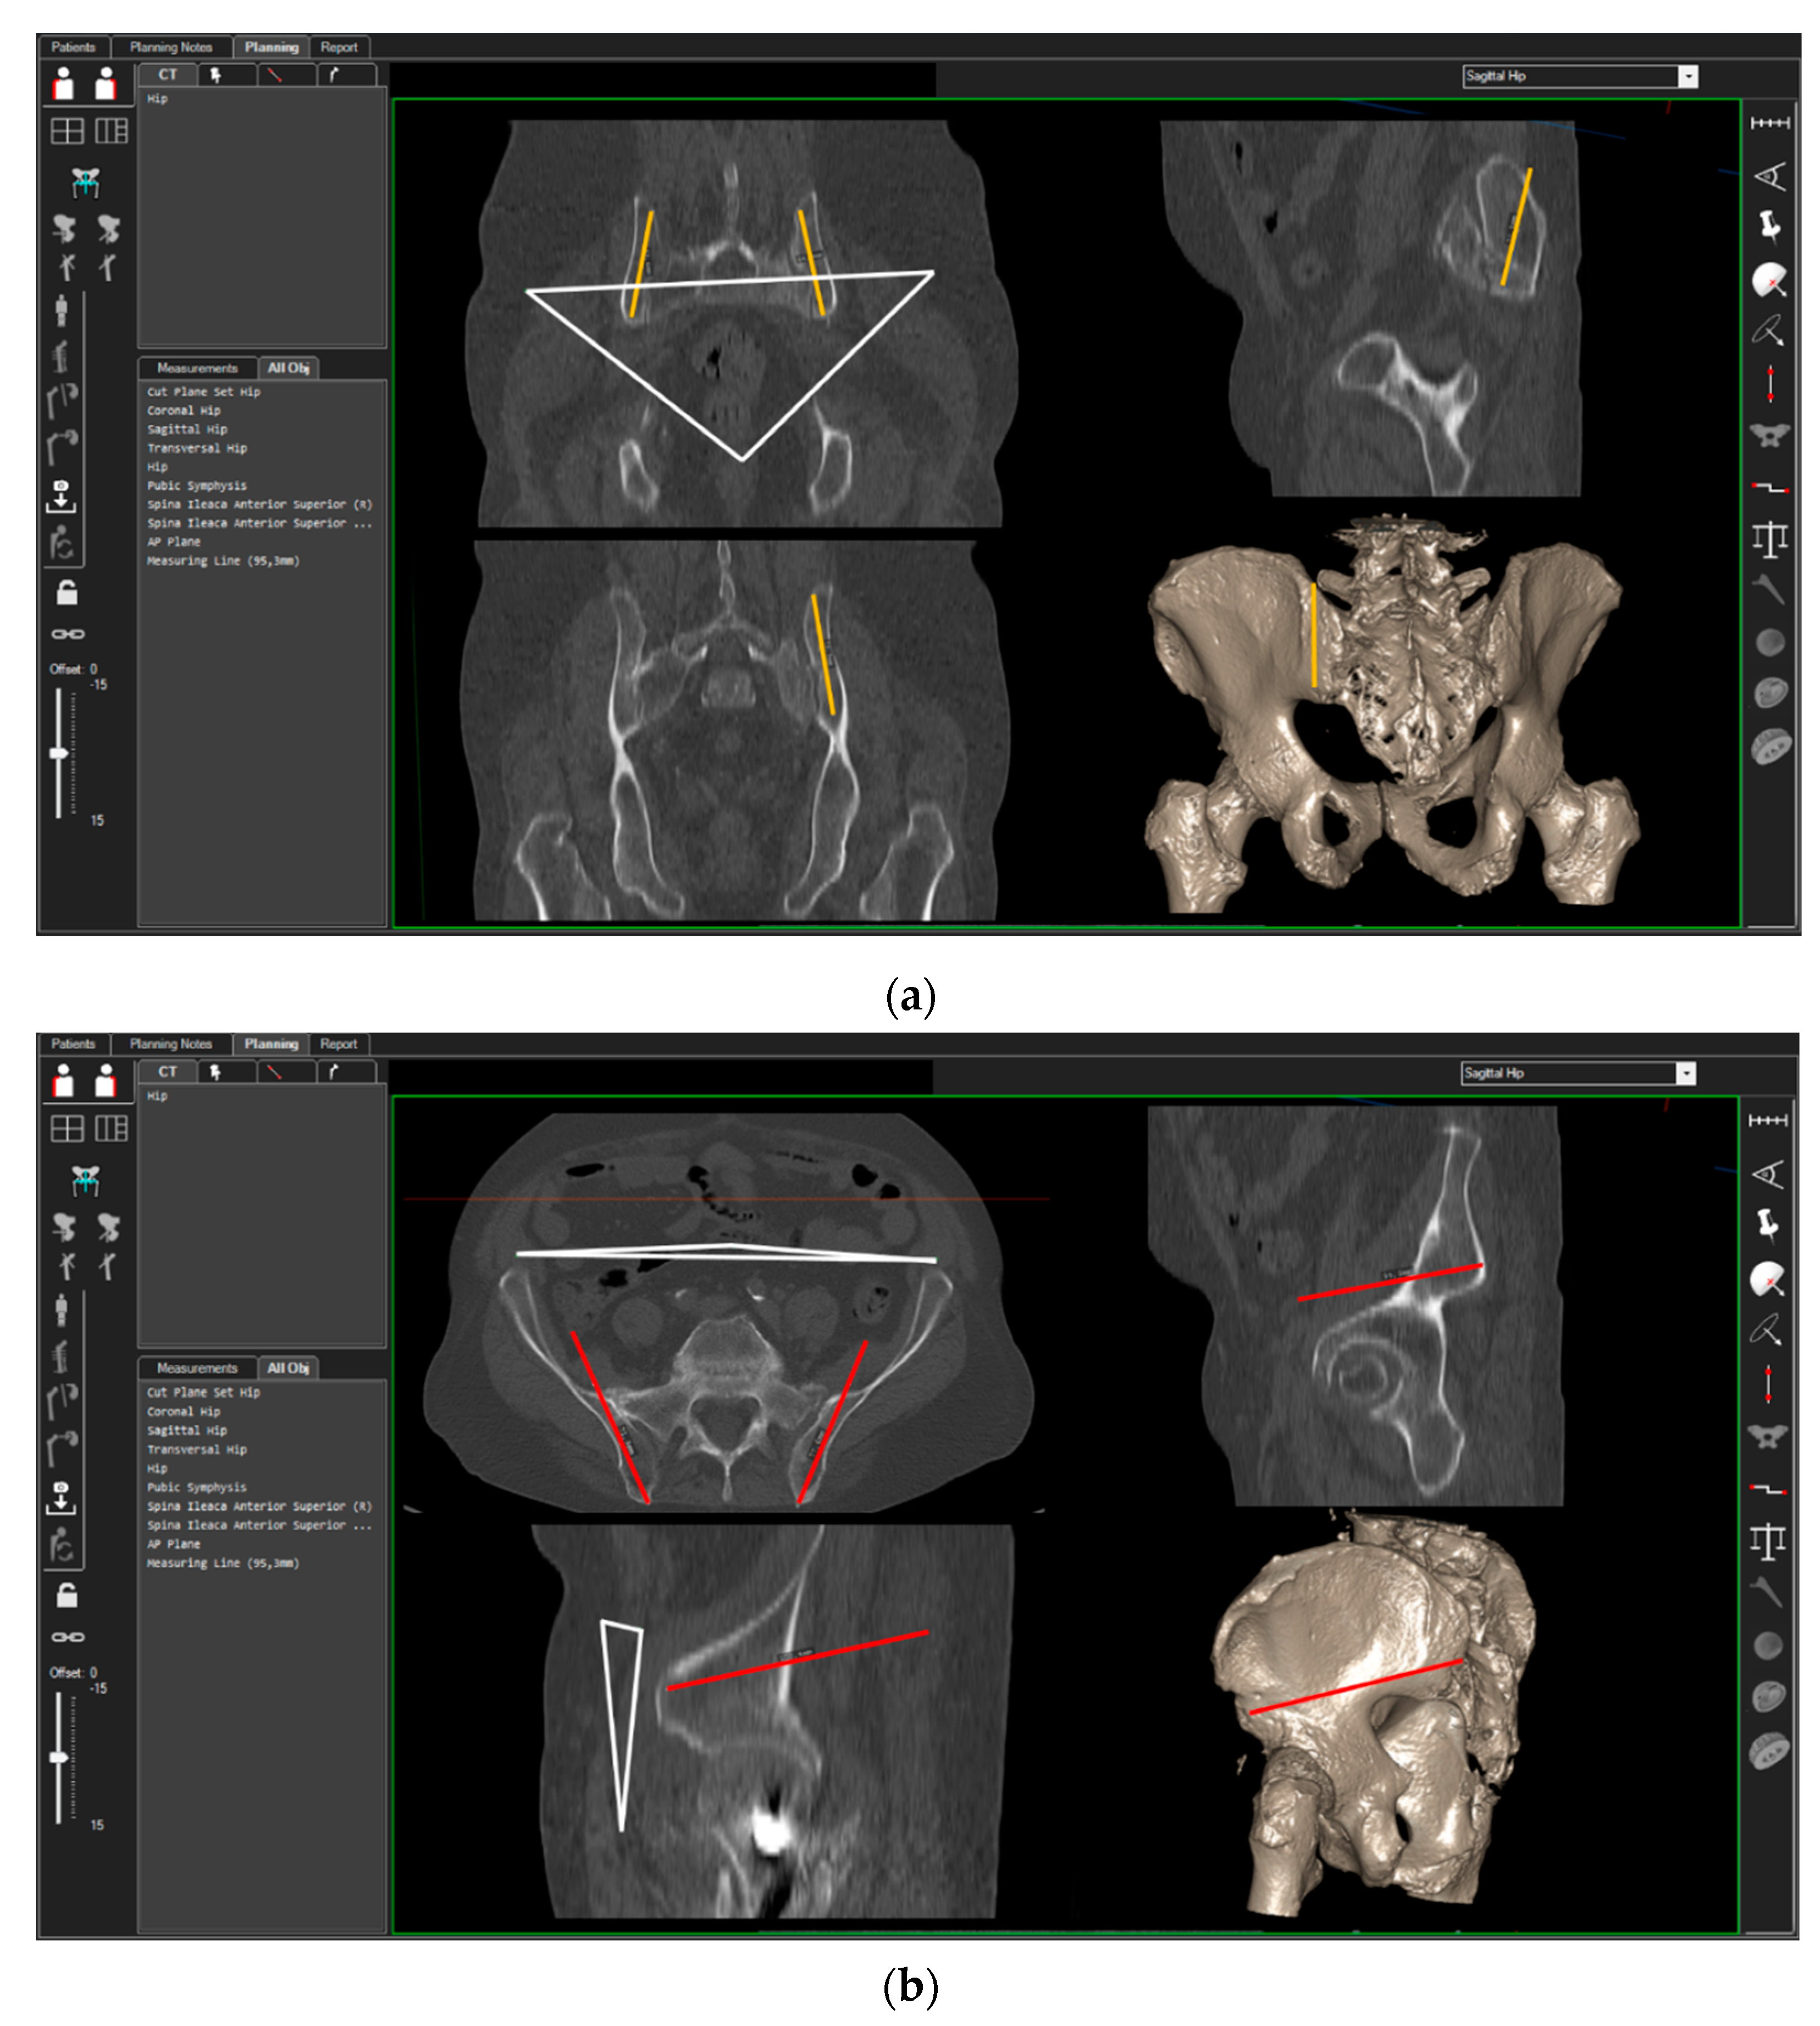

3D-CT scans of 40 randomly chosen patients (20 women, 20 men) were analyzed. CT measurements were carried out using the ‘semi-automatic’ function of a digital 3D‑CT-based planning software (Modicas, Erlangen, Germany). This software offers the possibility to assess the pelvis in three dimensions, to exactly determine the axes, and to automatically calculate angles and measure distances (Figure 2). First, the pelvis was virtually aligned in order to bring the anterior pelvic plane (APP) in congruence with the coronal plane in order to have a constant starting point. The APP is defined as the triangle between the pelvic symphysis and both anterior superior iliac spines (ASIS) [13] (Figure 2, please see the white triangle). In this context, fiducial landmarks from the frontal, sagittal, and axial view were identified and the specimens’ preoperative and postoperative position was carefully adjusted in order to exclude any rotational errors during the CT measurements.

Figure 2.

Setting of the 3D-CT-based measurement of the ilium screws in cranio-caudal (a) and dorso-ventral (b) orientation. White triangle = anterior pelvic plane (APP); orange line = position of the TIFIcc, red line = position of the TIFIdv.

The possible entry points for the iliac screws in the posterior iliac crest were identified. For the TIFI placed in cranio-caudal direction (TIFIcc), the entry point was chosen 1 cm lateral and 2 cm above the posterior superior iliac spine. The screw (Screw-TIFIcc) was oriented in the direction of the ischiadic notch parallel to the posterior gluteal line, as described previously [9]. For the alternative stabilization technique described by Schmitz et al. [10], the ileum screw was placed in a dorso-ventral direction (TIFIdv) and the entry point was chosen 1 cm above the posterior inferior iliac spine (PIIS). The screw (Screw-TIFIdv) was positioned in the direction of the anterior inferior iliac spine (AIIS).

The next step was to ensure that the screws were positioned in a way that they were surrounded by cancellous bone and that no contact to cortical bone existed.

After reaching the optimal position of the screws in the two different pelvic bone corridors, the angles in relation to the sagittal and axial plane of the pelvis were measured.